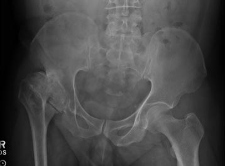

Chronic Collapse & Avascular Necrosis of Right Hip